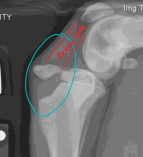

Condylar Fractures: Lateral > medial

Sig: Young dogs w/ Salter-Harris IV, older dogs w/ incomplete ossification of humeral condyle

Tx:

Lateral condyle: lag screw + anti-rotational K-wire

T or Y fracture: bilateral plates + screws